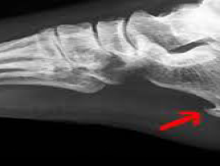

Patní ostruha a plantární fascitida